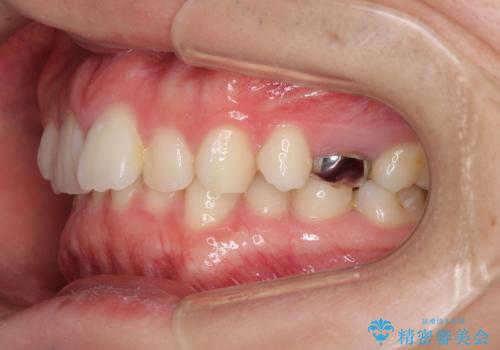

インビザラインによる矯正治療と奥歯のインプラント治療

- 咬み合わせと前歯のデコボコを気にして来院された患者様です。

前から5番目の永久歯が3本欠損しており、乳歯が残存している状態でしたが、インビザラインでも十分に対応可能と判断し、インビザラインにて矯正治療を行うこととしました。

右下の残存している乳歯は萌出しきれておらず、全く咬み合っていない状態であり、インビザラインにて移動できない可能性があるため、ワイヤー矯正の併用も念頭に置いて治療を開始しました。

今回は部分的にワイヤー矯正を用いましたが、右下の乳歯は全く動かなかったため、抜歯をした上でインプラントを埋入し、オールセラミッククラウンにて補綴治療を行いました。